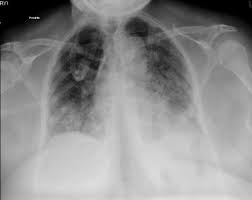

血管から血液が漏れる、つまりリーキーベッセルの状態になって、肺が水浸しになることで、息ができなくなります(Leukotoxin-diol: a putative toxic mediator involved in acute respiratory distress syndrome. Am J Respir Cell Mol Biol. 2001 Oct; 25(4):434-8)。